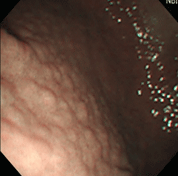

炎症も萎縮もない正常の胃粘膜